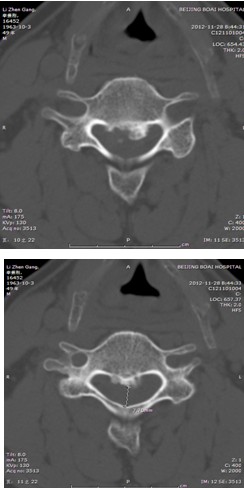

患者,男性,49岁,主因“行走不稳2个月伴右前臂麻木1个月”入院

2月前开始出现双下肢行走不稳,有踩棉花感,行走距离受限。1月前出现右侧前臂及手指麻木感。3周前诊断为“颈椎病”,保守治疗无改善,行走不稳症状加重

影像检查结果:

查体:右侧中指轻触觉、针刺觉减退,左侧上肢及双下肢感觉正常。

肌力:指屈肌群 左/右=5/4级,小指外展肌 左/右=5/4级。双侧膝腱反射亢进。双侧hoffman征阳性。肛门深感觉、自主肛门括约肌收缩存在。